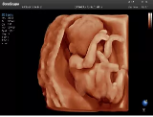

4容積探頭

積探頭是在二維圖像的基礎(chǔ)上,將連續(xù)采集的空間分布位置,經(jīng)過(guò)計(jì)算機(jī)重建算法,從而獲得完整的空間形態(tài)。

適用于:胎兒面部、脊柱和肢體等。

優(yōu)勢(shì)特點(diǎn):快速獲取、掃查連續(xù)均勻、解剖結(jié)構(gòu)顯示為容積數(shù)據(jù)、準(zhǔn)確進(jìn)行容積測(cè)量。